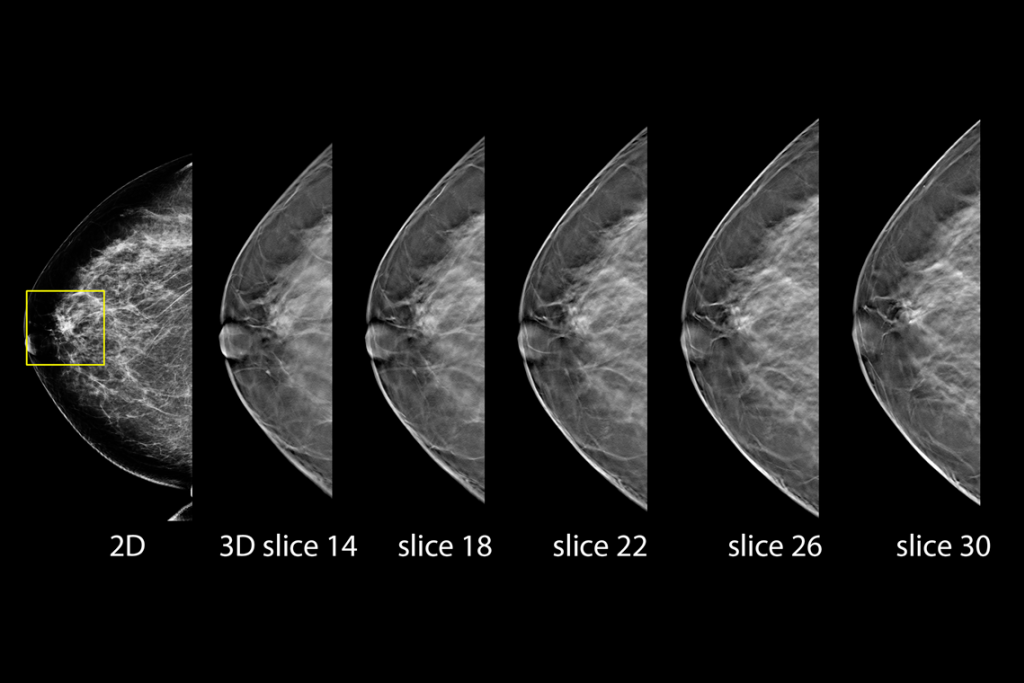

Clinical images of breast scan mammography

Clinical images of breast scan with suspicious Lesion

Clinical images of breast scan

Clinical images of breast scan with fatty breast